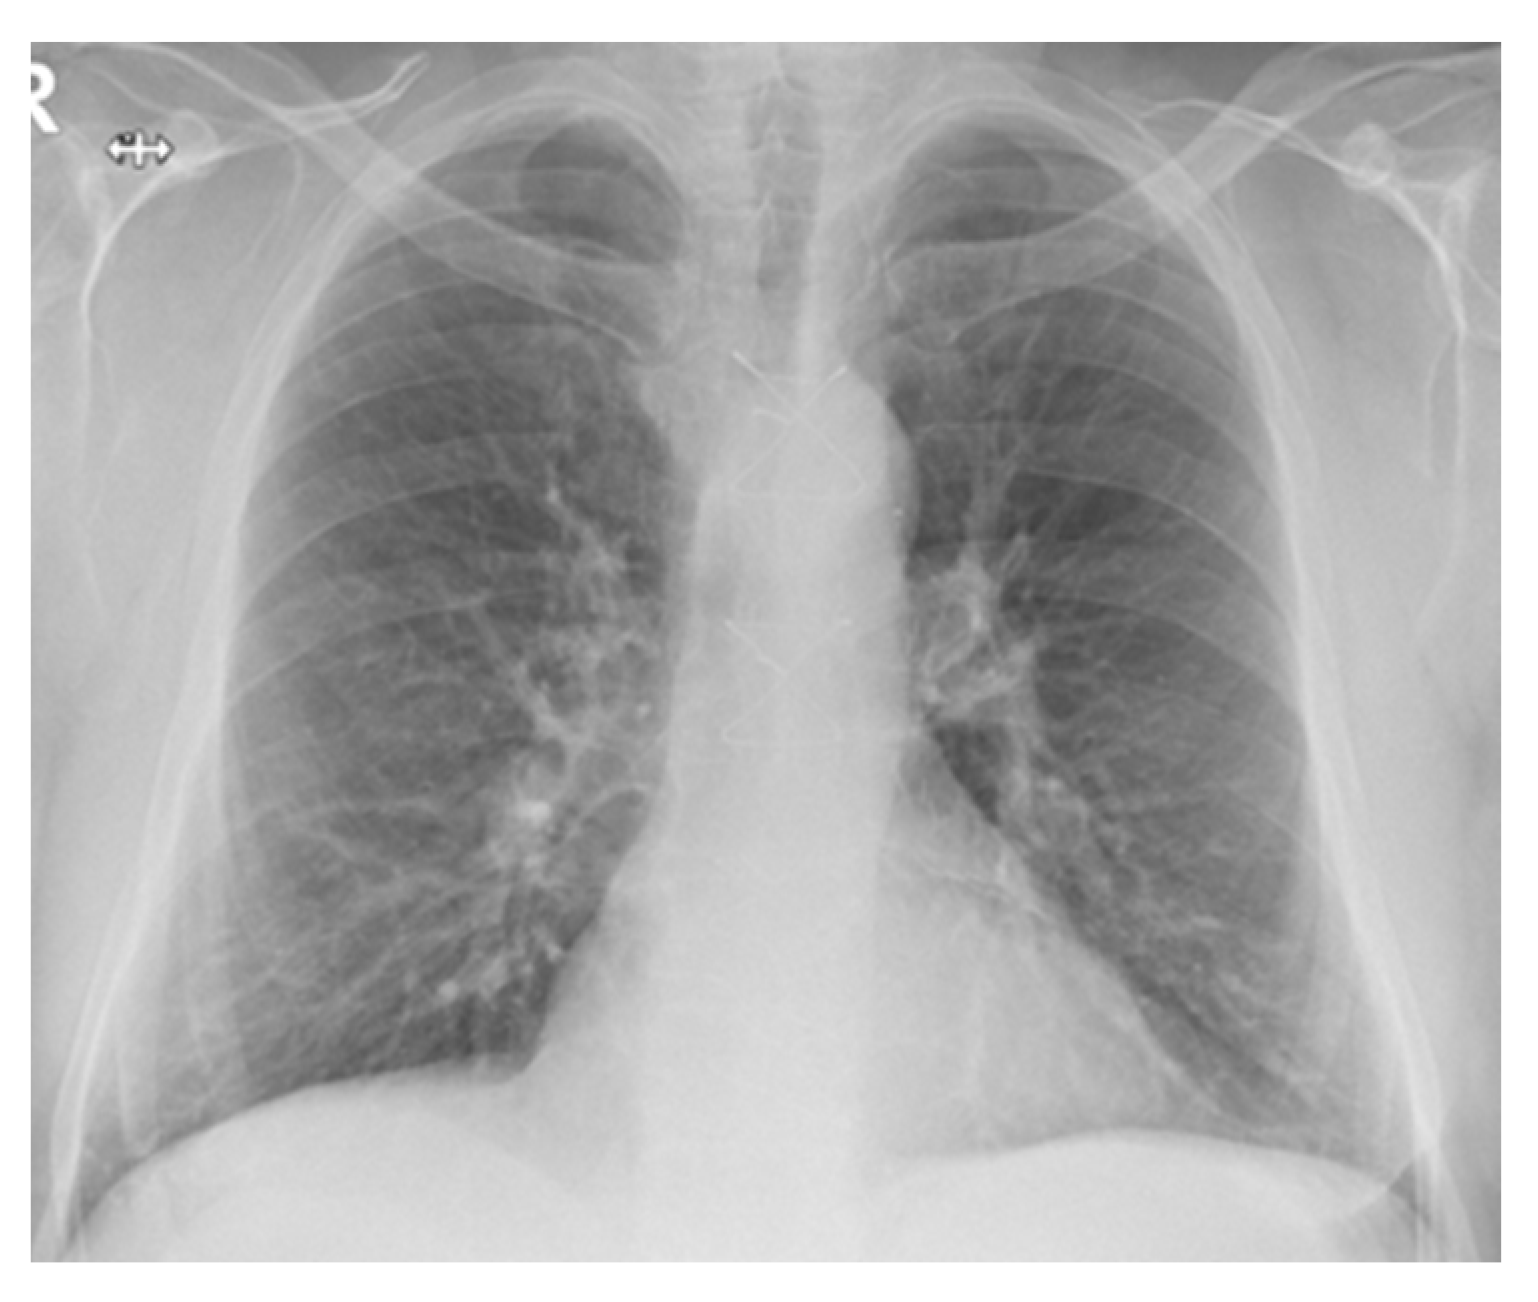

2.2. Case Presentation 2

2.3. Case Presentation 3